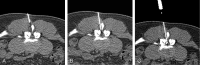

Lumbar epidural injections are typically performed blindly or with fluoroscopic guidance. CT fluoroscopy (CTF) can be used to guide needle placement precisely and rapidly, allowing visualization of the optimal needle path and identifying potential problems such as severe stenosis and synovial cysts before needle insertion. Operator and patient radiation dose is minimal when using the intermittent CTF technique and low mAs. By using this technique, just more than 2000 epidural steroid injections have been performed with no major complications. CTF is a useful guidance tool when performing lumbar epidural injections.